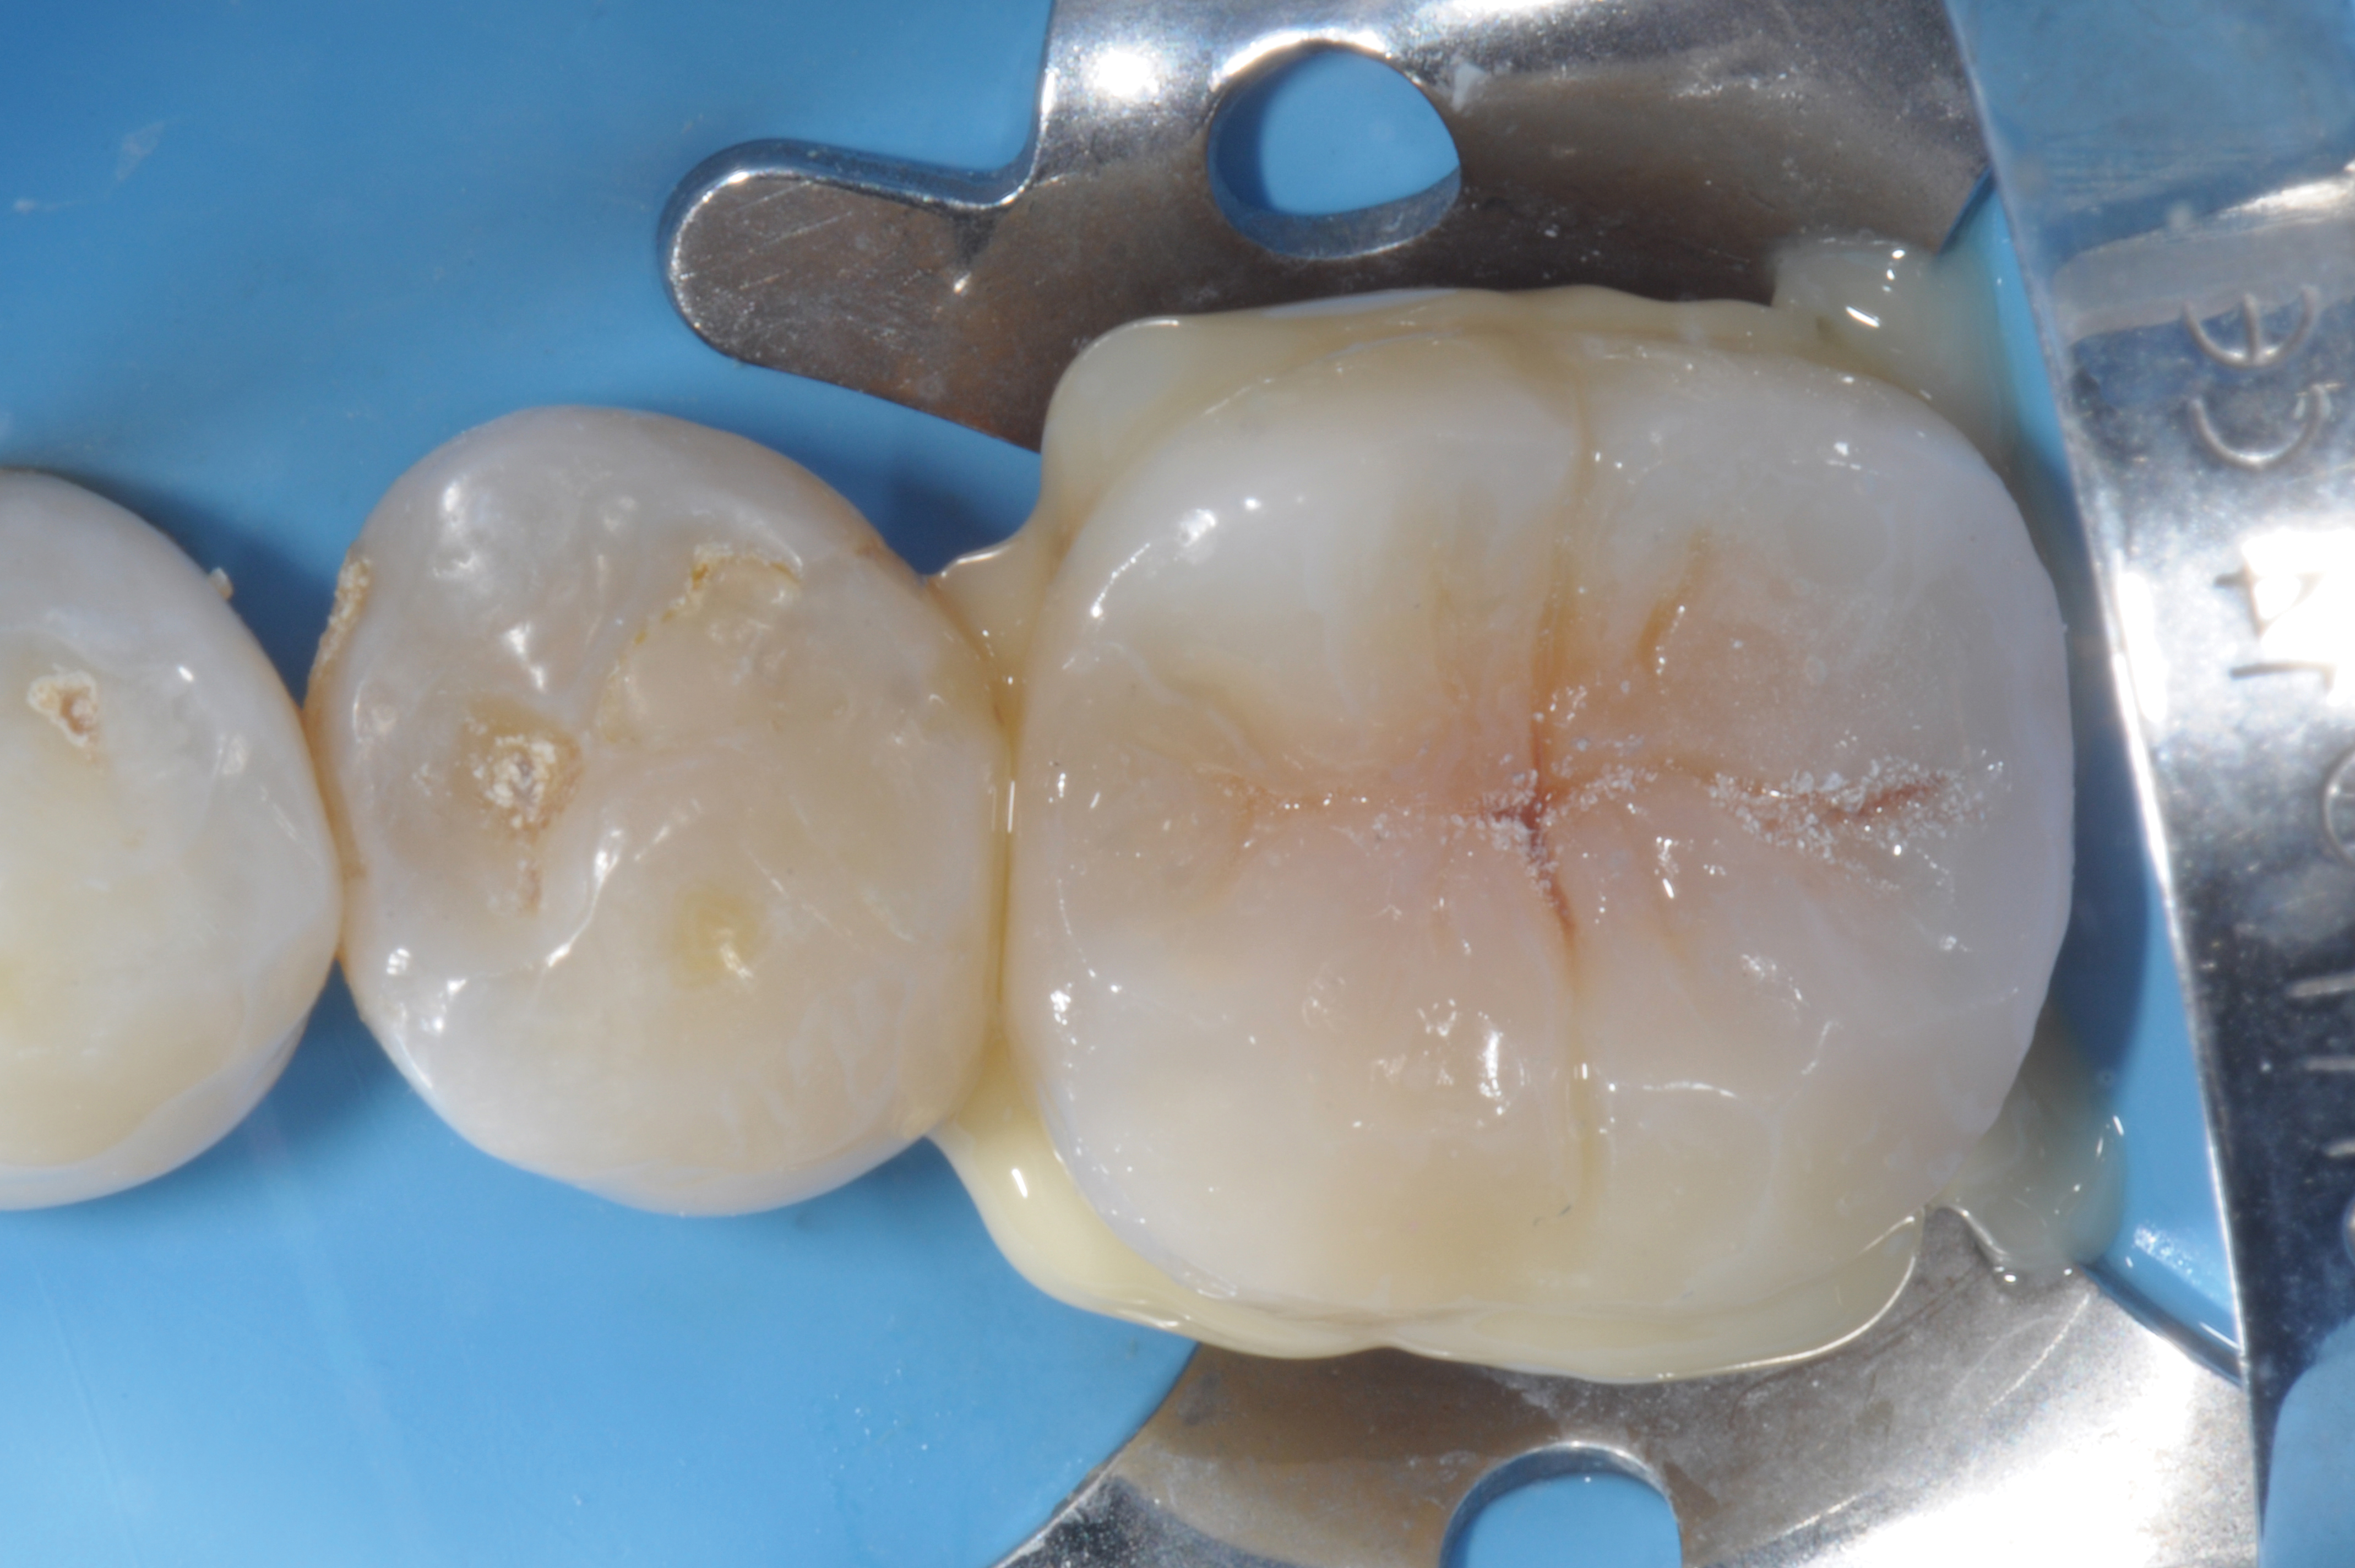

Fig 3. Cementation of an indirect composite restoration.

Figure 3

When following a protocol of cementation using an adhesive system, constant rubber dam isolation and careful hand finishing are necessary to provide predictable clinical results (Figure 1 through Figure 4).2